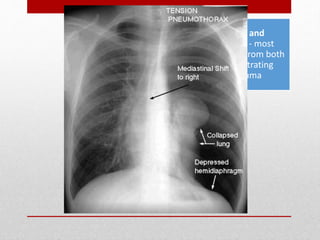

Tension pneumothorax

• presumed in any patient manifesting

respiratory distress and hypotension

in combination with any of the

following physical signs:

• tracheal deviation away from the

affected side

• lack of or decreased breath sounds

on the affected side,

• subcutaneous emphysema on the

• Distnded neck veins

• Tube thoracostomy in the

midaxillary line should be

performed immediately in the

ED before a chest radiograph

is obtained.

• Recent studies suggest that

preferred location for needle

decompression may be the

fifth intercostal space in the

anterior axillary line due to

body habitus.